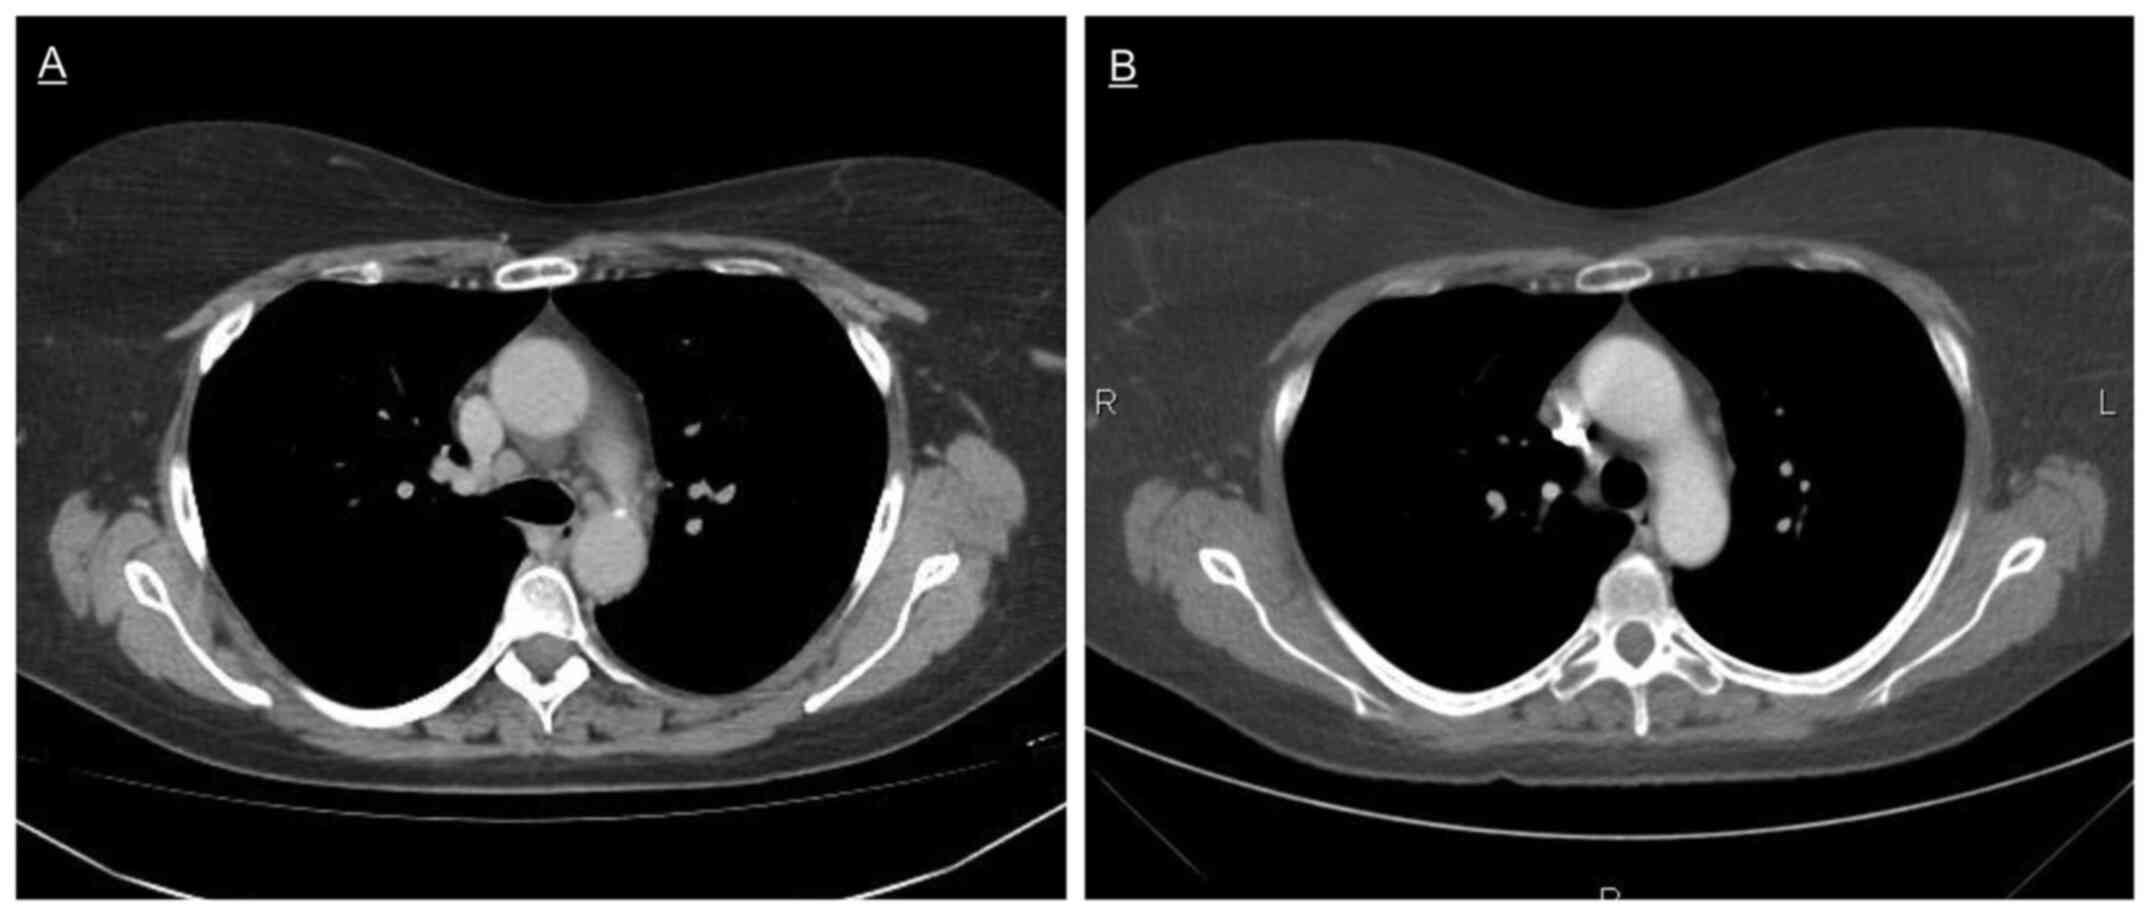

Mediastinal and hilar sarcoid‑like reaction in a patient treated with dabrafenib and trametinib for metastatic melanoma: A case report and review of the literature

BRAF/MEK inhibitors are considered standard of care in the treatment of advanced BRAF‑mutated malignant melanoma, and have been, in rare cases, associated with granulomatous reactions, mostly limited to skin lesions. The present study reported the case of a patient with metastatic melanoma developing a sarcoid‑like reaction manifesting as asymptomatic mediastinal and right hilar lymphadenopathy while on antineoplastic therapy with dabrafenib and trametinib. To the best of our knowledge, this is the first reported case of isolated lymphadenopathy as a manifestation of drug‑induced sarcoid‑like reaction under dabrafenib and trametinib. Overall, only 17 other cases of granulomatosis have been reported in the literature. Although uncommon, such reactions should be considered in the differential diagnosis of lymph node enlargement, and distinguishing them from tumor progress is important and can be challenging in clinical practice.

Figure 1

Figure 2